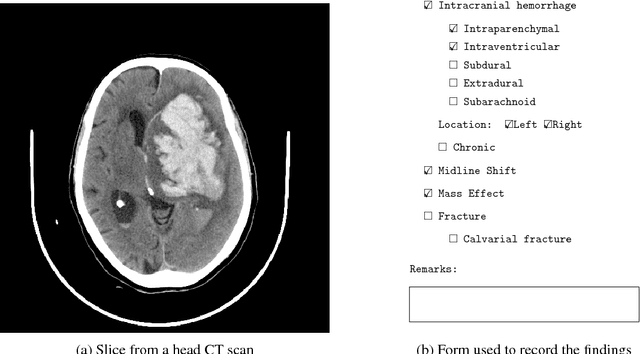

Abstract:Importance: Non-contrast head CT scan is the current standard for initial imaging of patients with head trauma or stroke symptoms. Objective: To develop and validate a set of deep learning algorithms for automated detection of following key findings from non-contrast head CT scans: intracranial hemorrhage (ICH) and its types, intraparenchymal (IPH), intraventricular (IVH), subdural (SDH), extradural (EDH) and subarachnoid (SAH) hemorrhages, calvarial fractures, midline shift and mass effect. Design and Settings: We retrospectively collected a dataset containing 313,318 head CT scans along with their clinical reports from various centers. A part of this dataset (Qure25k dataset) was used to validate and the rest to develop algorithms. Additionally, a dataset (CQ500 dataset) was collected from different centers in two batches B1 & B2 to clinically validate the algorithms. Main Outcomes and Measures: Original clinical radiology report and consensus of three independent radiologists were considered as gold standard for Qure25k and CQ500 datasets respectively. Area under receiver operating characteristics curve (AUC) for each finding was primarily used to evaluate the algorithms. Results: Qure25k dataset contained 21,095 scans (mean age 43.31; 42.87% female) while batches B1 and B2 of CQ500 dataset consisted of 214 (mean age 43.40; 43.92% female) and 277 (mean age 51.70; 30.31% female) scans respectively. On Qure25k dataset, the algorithms achieved AUCs of 0.9194, 0.8977, 0.9559, 0.9161, 0.9288 and 0.9044 for detecting ICH, IPH, IVH, SDH, EDH and SAH respectively. AUCs for the same on CQ500 dataset were 0.9419, 0.9544, 0.9310, 0.9521, 0.9731 and 0.9574 respectively. For detecting calvarial fractures, midline shift and mass effect, AUCs on Qure25k dataset were 0.9244, 0.9276 and 0.8583 respectively, while AUCs on CQ500 dataset were 0.9624, 0.9697 and 0.9216 respectively.